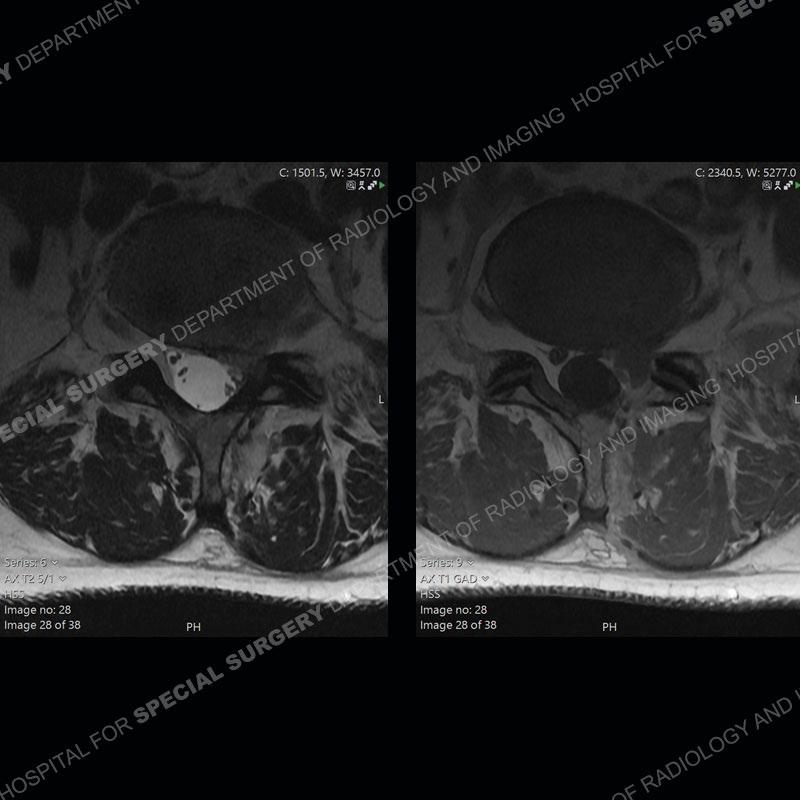

Post operative changes are seen on the left side at L5-S1 where there is near complete removal of the left sided L5 lamina, partial resection of the left L5-S1 facet joint, and resection of the left sided ligamentum flavum. In the anterolateral epidural space about the subarticular recess is a mass that demonstrates similar T1 and T2 signal characteristics to the adjacent degenerated disc. There is enhancement about the periphery of the mass, but the majority of this somewhat geographic or polyploid mass demonstrates no enhancement. The mass exerts prominent mass effect on the left S1 axillary sleeve/proximal nerve root. The left S1 nerve root shows enlargement and increased enhancement as compared to the contralateral right side.

Diagnosis: Recurrent Disc Herniation

Not as much of a diagnostic dilemma as some other cases but more so just a very nice example of what can be a difficult assessment at times. The evaluation of granulation tissue/scar/epidural fibrosis vs. disc herniation particularly in the earlier post operative period can be very difficult. Clues that can assist in identifying a disc herniation are a more geographic or polypoid nature to the mass, signal characteristics similar to the adjacent degenerated disc, mass effect upon the thecal sac/adjacent neural structures, and a typical enhancement pattern. As the disc material is avascular, as long as imaging is performed in a relatively rapid fashion after contrast administration (within 20-30 minutes), the granulation tissue around the disc will enhance but the disc material itself will not. If there is a marked delay between contrast administration and imaging, there may be diffusion of contrast into the disc making the assessment very difficult. The marked utility of contrast to help delineate disc vs. scar has led to our institution employing contrast fairly uniformly within the first two years following surgery.